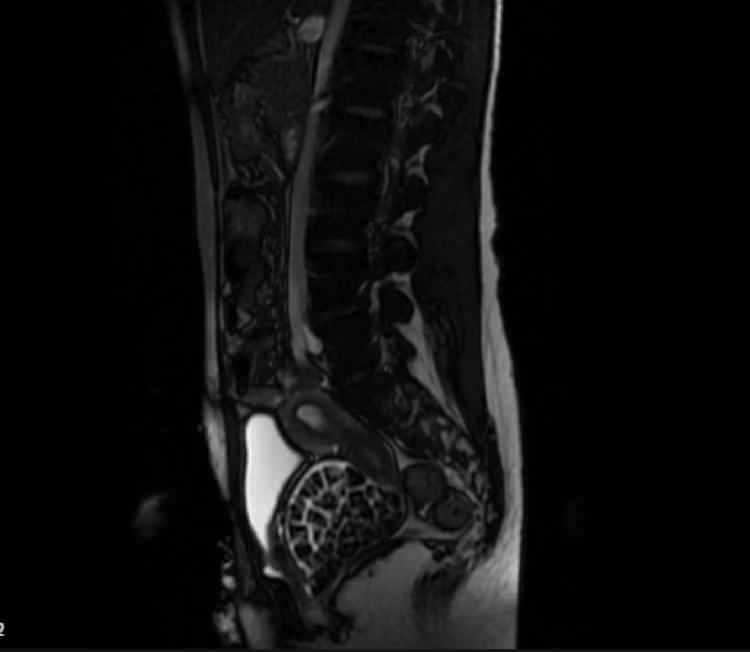

Hastasının durumuna yönelik konuşan Üroloji Uzmanı Doç. Dr. Erkan Erkan, "Hastamız 50 binde bir görülen bir anomaliden dolayı art arda ameliyatlar geçirdiğini öğrendik. Mesanesinin olması gereken yerin hemen arka kısmında taşlarla dolu bir kese olduğunu gördük. O kadar taş beklemiyorduk, çok şaşırdık. Literatürde sanırım yayınlanmış 2'nci vaka olacak" dedi.